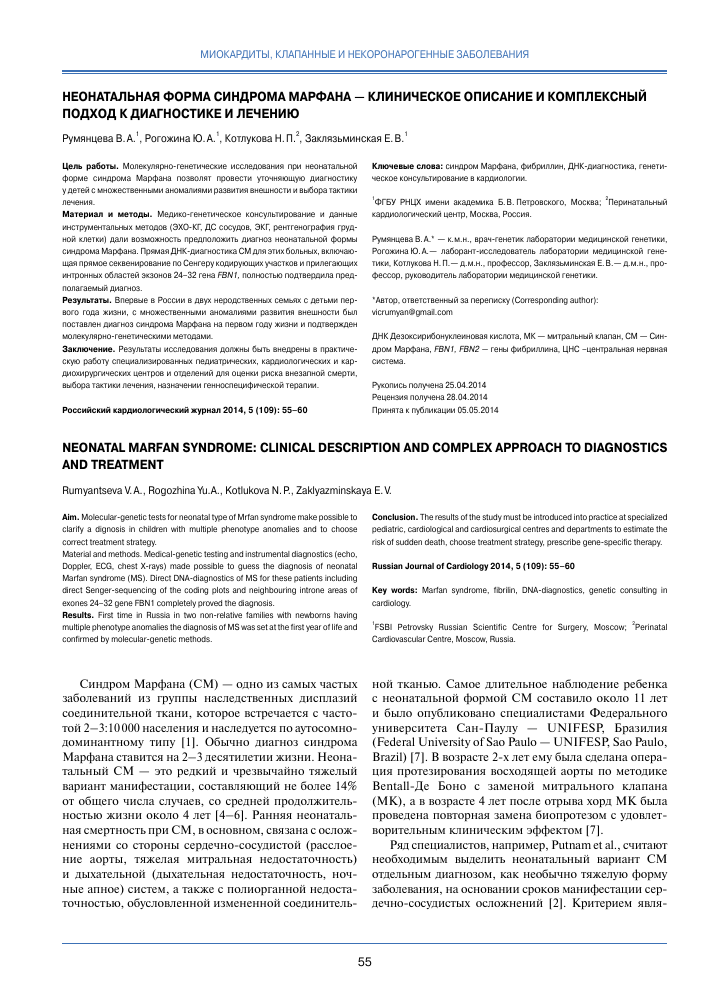

Neonatalnaya forma sindroma marfana klinicheskoe opisanie i kompleksnyj podhod k diagnostike i lecheniyu tema nauchnoj stati po klinicheskoj medicine chitajte besplatno tekst nauchno issledovatelskoj raboty v elektronnoj biblioteke kiberleninka (Тип файлу jpg)

Neonatalnaya Forma Sindroma Marfana Klinicheskoe Opisanie I Kompleksnyj Podhod K Diagnostike I Lecheniyu Tema Nauchnoj Stati Po Klinicheskoj Medicine Chitajte Besplatno Tekst Nauchno Issledovatelskoj Raboty V Elektronnoj Biblioteke Kiberleninka